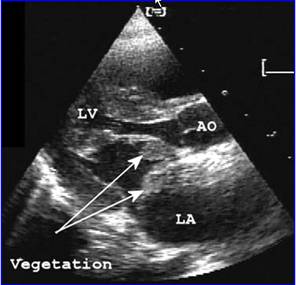

检查:心电图、胸部X线、超声心动图、右心导管检查[4] 。